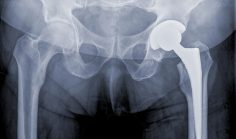

_ Hip HealthDual Mobility Hip Replacement Reduces Risk of Dislocation By Sondra Forsyth articleMore than 330,000 total hip replacements are performed in the United States each year. Overall, it is a highly successful … Read More→

_ Hip HealthNumber of Hip Replacements Rising, Number of Surgeons Falling By articleTotal hip replacements nearly doubled among middle aged patients over the past several years. At the same time, there’s been … Read More→